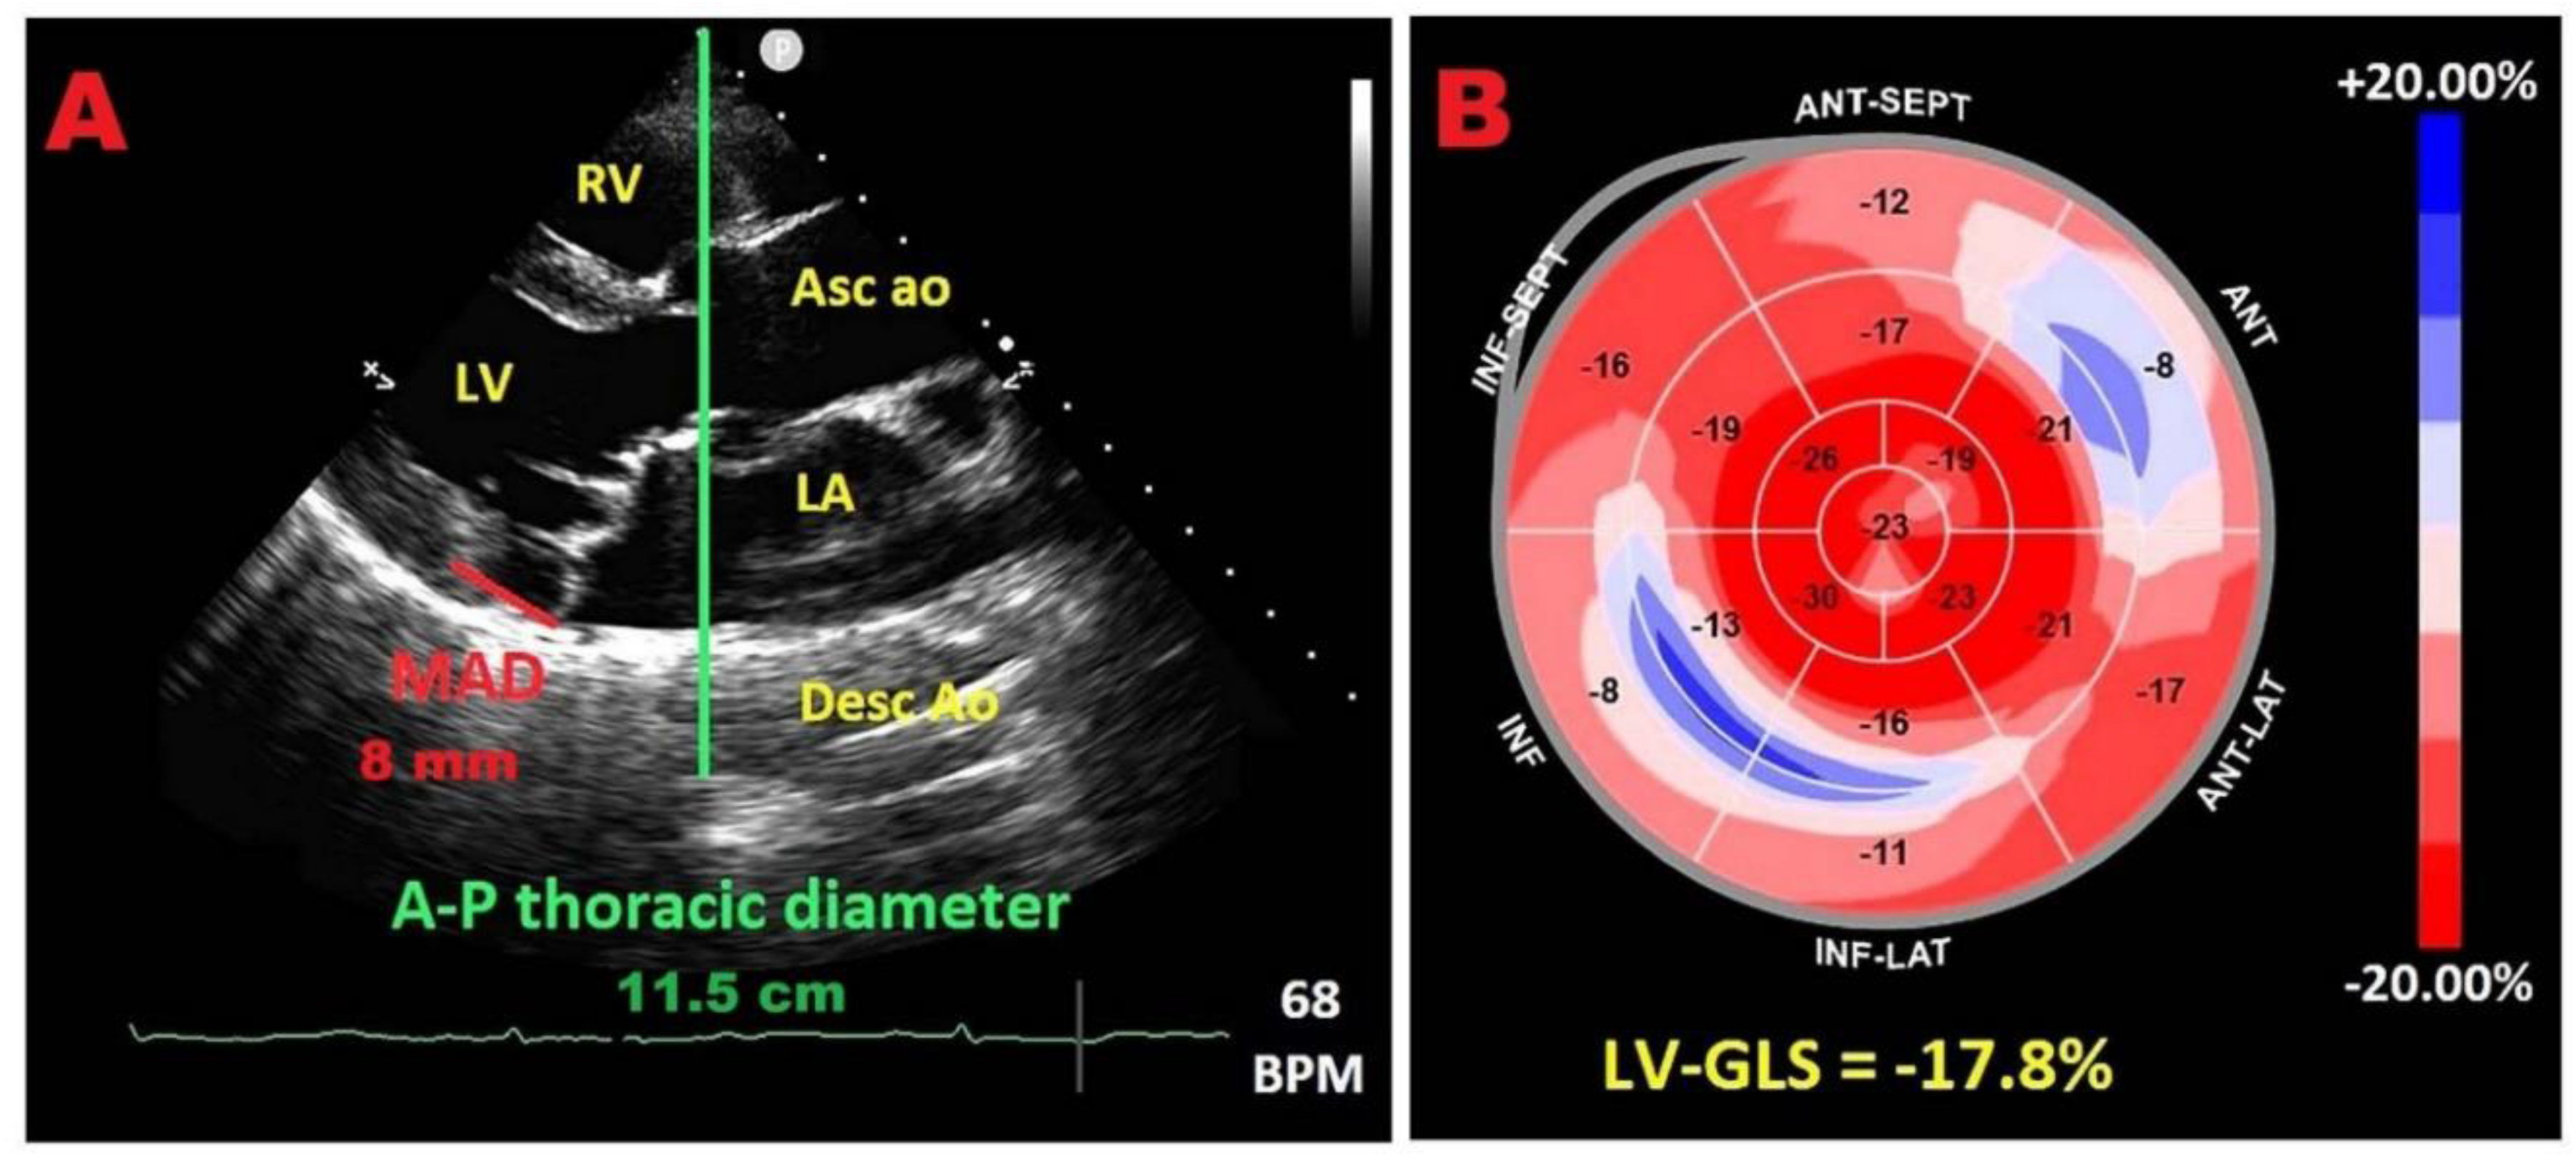

7.1. Modified Haller Index

7.2. Relationship between chest wall conformation and MAD distance in PMR with MVP

7.3. Potential link between concave chest morphology and a “benign MAD phenotype”